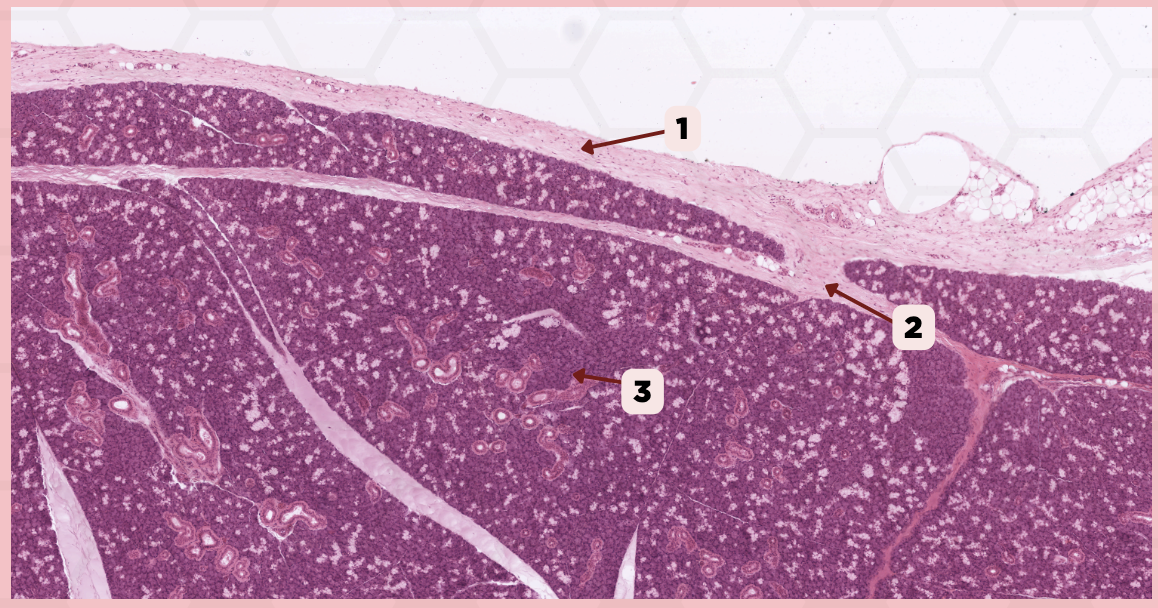

Lip

What specimen is showed in the picture?

Labial Glands (in the Mucosa)

Identify the structure labeled as 1.

Skeletal Muscle Cells

Identify the structure labeled as 2.

Lamina Propria

Identify the structure labeled as 3.

Mucosa

Identify the structure labeled as 4.

Lip

What specimen is showed in the picture?

Skeletal Muscle Fibers

Identify the structure labeled as 1.

Labial Glands

Identify the structure labeled as 2.